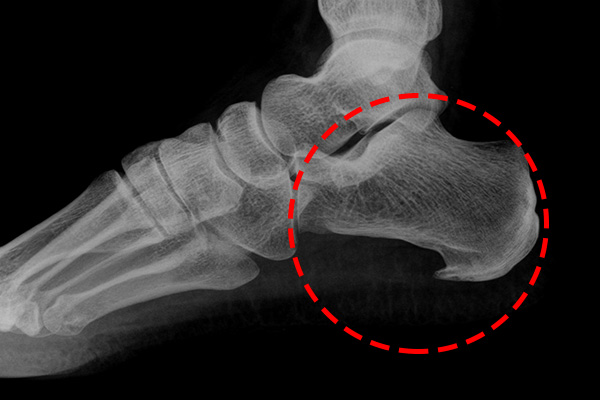

발바닥통증의 원인 고통성 족부 변형 (뼈 돌출 등)

- 발바닥의 뼈나 관절의 이상으로 인해 통증이 발생할 수 있습니다. 뼈의 돌출이나 과도한 뼈 성장(예: 발가락의 뼈가 튀어나오는 경우) 등이 그 예입니다. 이 경우 신발이 맞지 않거나 발에 가해지는 압력이 증가하여 통증이 유발됩니다.